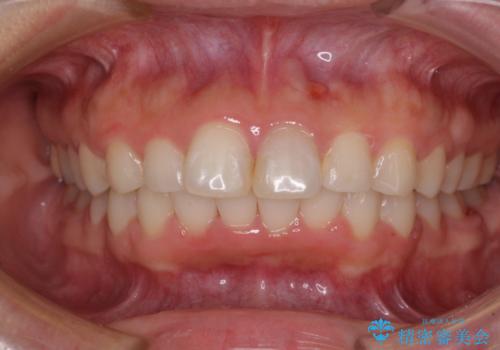

もう少しデコボコを改善したかったのですが、ご本人の希望もあり、装置を除去しました。

後戻りを防止するため、舌側を細いワイヤーによる保定を行いました。